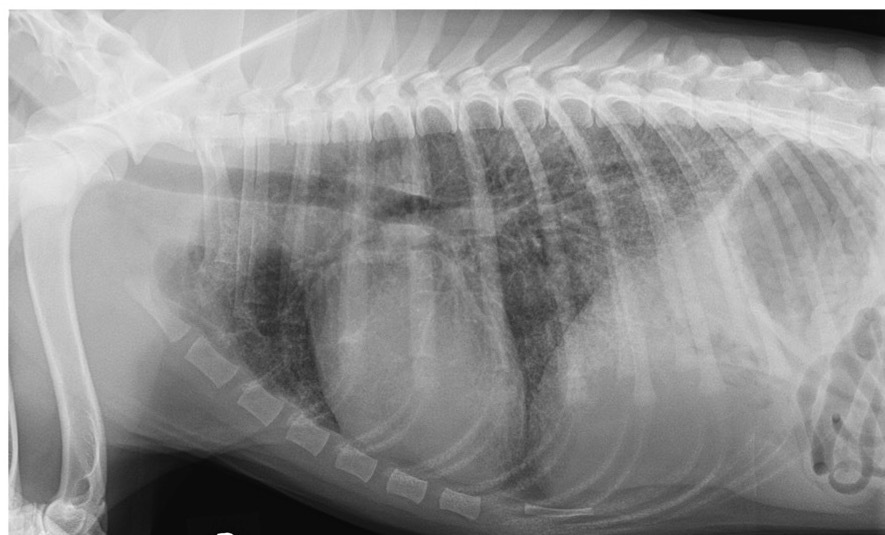

Which lung pattern is shown in Case 1? Justify your answer.

A

Interstitial

There is a diffuse increase in radiodensity (greying-out, lace curtain) but no border obliteration